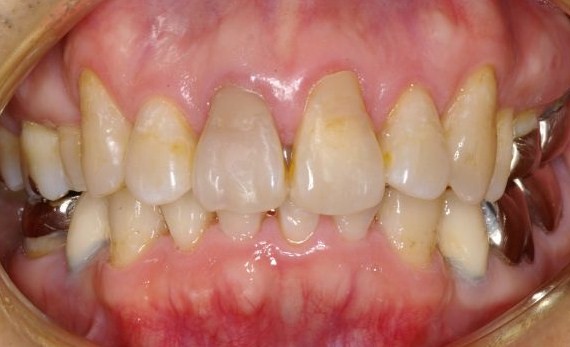

| A手術当日に仮歯のブリッジが入るオールオン6 (ノーベルバイオケア使用症例) |

| この症例の場合は、顎の骨の幅は、あまり広くはなかったですが 上顎洞までの距離があって13mmの長さのインプラントを選択することができたので 6本のインプラント(条件が整えばノーベルバイケアインプラント推奨)で行いました。 |

| これは、インプラントを入れた当日に仮の歯をブリッジにしていれた状態のレントゲンです。 インプラントを埋入するときのトルクが35N(ニュートン)から40Nの範囲で埋めることができないと その場で仮歯を入れて咬めるようにして帰っていただくこと(即時荷重)が出来ません。 骨がある程度硬くないと無理ですし、また、軟らかい骨でも削るのではなく押し広げるように形成することによって このトルクを作るようにします。 最初のドリルの感じで、どのように押し広げれば 適正なトルクで埋入することが出来るかがイメージ出来なければ無理です。 また、骨の幅がギリギリでシミュレーションとの誤差が0.3mm以内の精度でしかも方向を合わせなければいけません。 文字通り職人技です。 これが出来る歯科医師は、兵庫県でも極少数だと自負しております。 |

先の症例@の方と同じく、笑気麻酔などを使用しました。 総入れ歯と、このようになるのとでは咬めることはもちろん、気分が違ってきて若返られています。 |